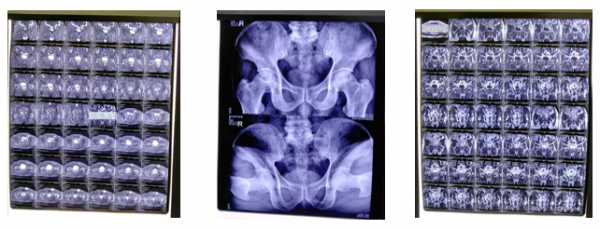

病例一:强直性脊柱炎

25岁董某,患病十余年,多方治疗无效。经脑针治疗,僵硬与疼痛明显缓解,活动能力显著提升。